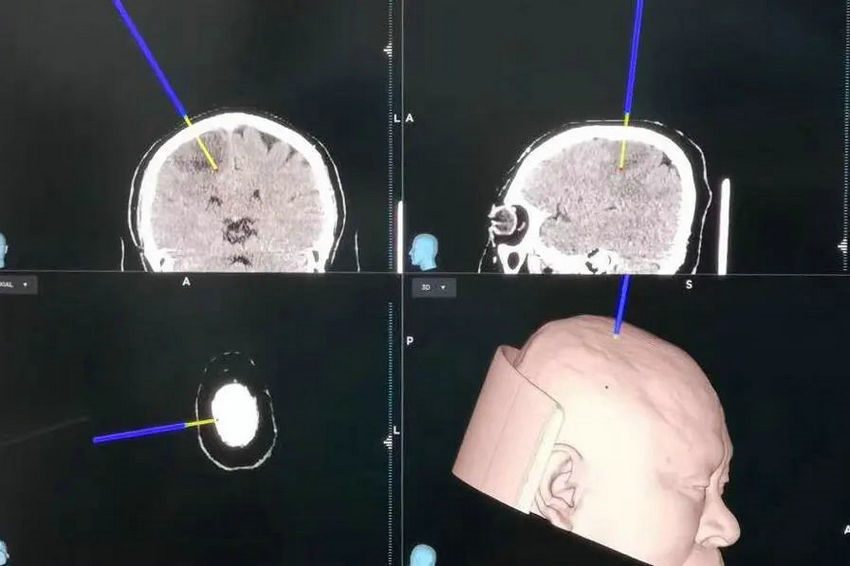

▲ 肿瘤及周围组织三维重建

通过治疗团队充分的术前沟通谈话,确定其可以接受既定手术方案。通过对肿瘤及周围脑组织、传导束、动静脉血管进行多模态三维重建,手术组医师制定了详细的手术计划。

▲ 神经外科手术导航

手术如期开始,在神经外科手术导航技术辅助下,精准定位肿瘤病灶,尽可能减少手术创伤。完成相应的手术步骤后,麻醉医师对其进行术中唤醒,赵先生完全清醒、逻辑清晰,但没有感到任何疼痛,还和手术医师一问一答地“聊起来”。在聊天的过程中,通过功能区皮层电刺激技术及神经电生理监测技术,确认了脑功能区皮层的准确位置和安全的手术路径,采用肿瘤荧光示踪技术,明确了安全的手术范围。肿瘤切除后,手术室内即刻行CT扫描验证,术后赵先生再次醒来,四肢运动及感觉功能完好。目前,经过术后的治疗,患者左侧肢体运动及感觉功能已经恢复至正常。